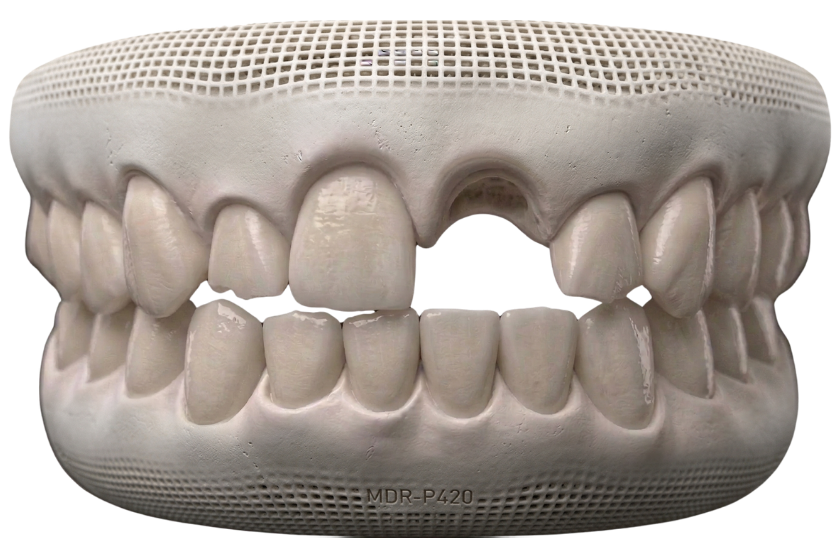

Missing Teeth

Gaps in your smile can impact chewing efficiency and cause surrounding teeth to shift over time.